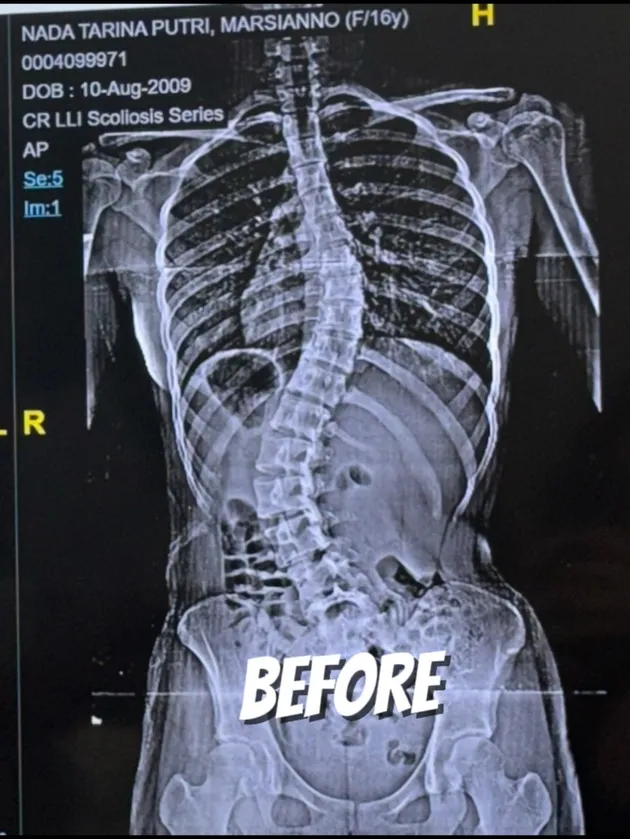

Nada Tarina Putri shares her experience after undergoing scoliosis surgery a month ago. Through her social media post, she shows the condition of her spine before and after the major surgery.